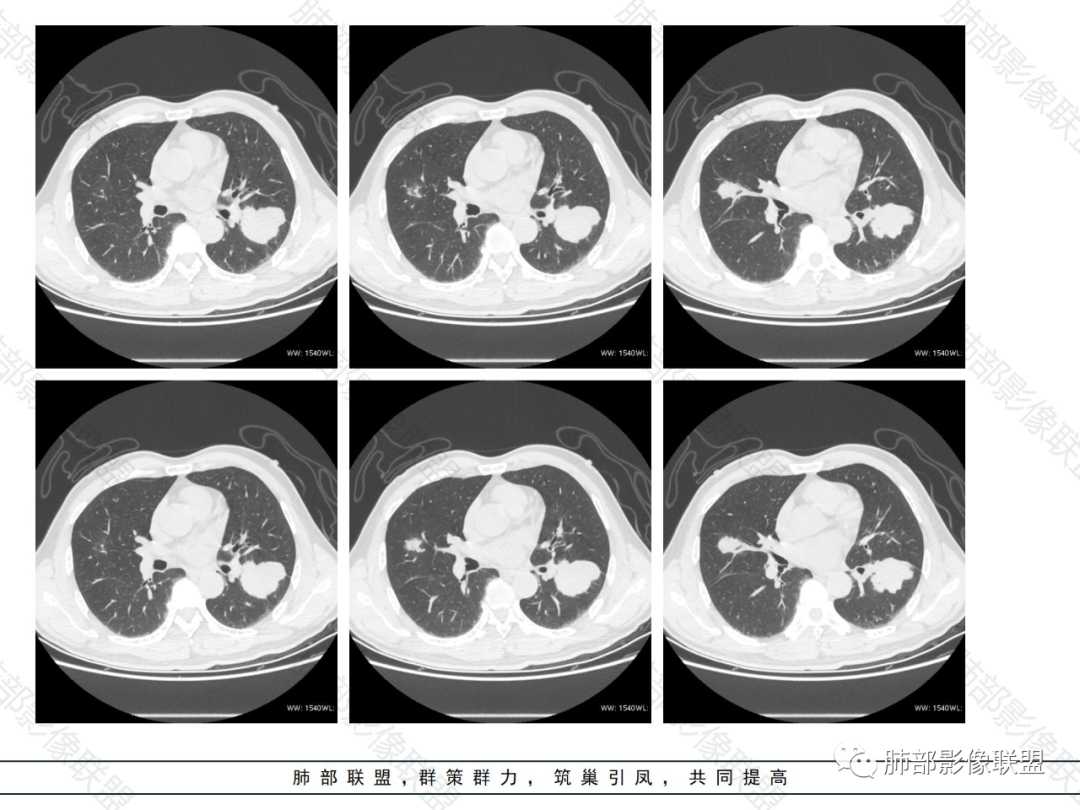

外围胸膜下、支气管血管束分布

实变,密度较均匀

病灶的边缘平直、膨隆都有

内部支气管稍扩张,直达远端,或受压变形、移位

均匀强化

内部血管走形自然,稍纤细

支气管通畅、稍扩张、移位——不支持支气管来源

提示间质来源、周围肺实质来源

疾病普:淋巴瘤、血管炎性病变、隐球菌

占位效应与收缩性均匀,内部支气管稍扩张,或推移,淋巴瘤要考虑

1.病灶分布:因为肺内淋巴瘤主要侵犯对象是肺间质和支气管黏膜下组织,病灶主要位于在沿支气管血管束分布、肺间质及胸膜下,病灶可跨叶分布。

2.病灶的密度:密度均匀,部分病灶内可见空洞及气液平,轻中度均匀强化。

3.支气管充气征伴或不伴支气管扩张:肿瘤细胞沿肺间质及支气管黏膜下组织浸润,支气管管壁未见明显破坏,管腔内未见肿瘤细胞充填,呈现充气支气管征;充气支气管走行自然,无扭曲、僵硬,内壁管腔光滑,支气管管壁见增厚并常有管腔的扩张,含气支气管可呈串珠样不均匀扩张,扩张明显处呈空腔样或皂泡样的囊状含气影;支气管扩张目前有两种意见:一是由于肿瘤组织起源于肺间质,肿瘤沿或跨越脏器解剖结构生长,原有解剖结构残留,周围增生的纤维结缔组织牵拉导致支气管扩张;二肿瘤侵犯支气管粘膜下植物神经丛致平滑肌张力丧失;而这类支气管扩张在肿瘤治疗后有时可消失。

支气管充气征伴扩张

4.血管造影征:肿瘤组织浸润引起间质增厚、肺泡壁破坏、肺泡腔充填,而周围充盈血管走行自然,未受肿瘤侵犯。血管造影征

5.病灶的边缘:有膨隆,浅分叶,也有平直、收缩,平直收缩是因为肿瘤组织浸润致肺泡塌陷及周围纤维组织增生,牵拉正常的肺组织向病灶中心形成聚拢状改变,似呈“炎性”改变。

膨隆、平直